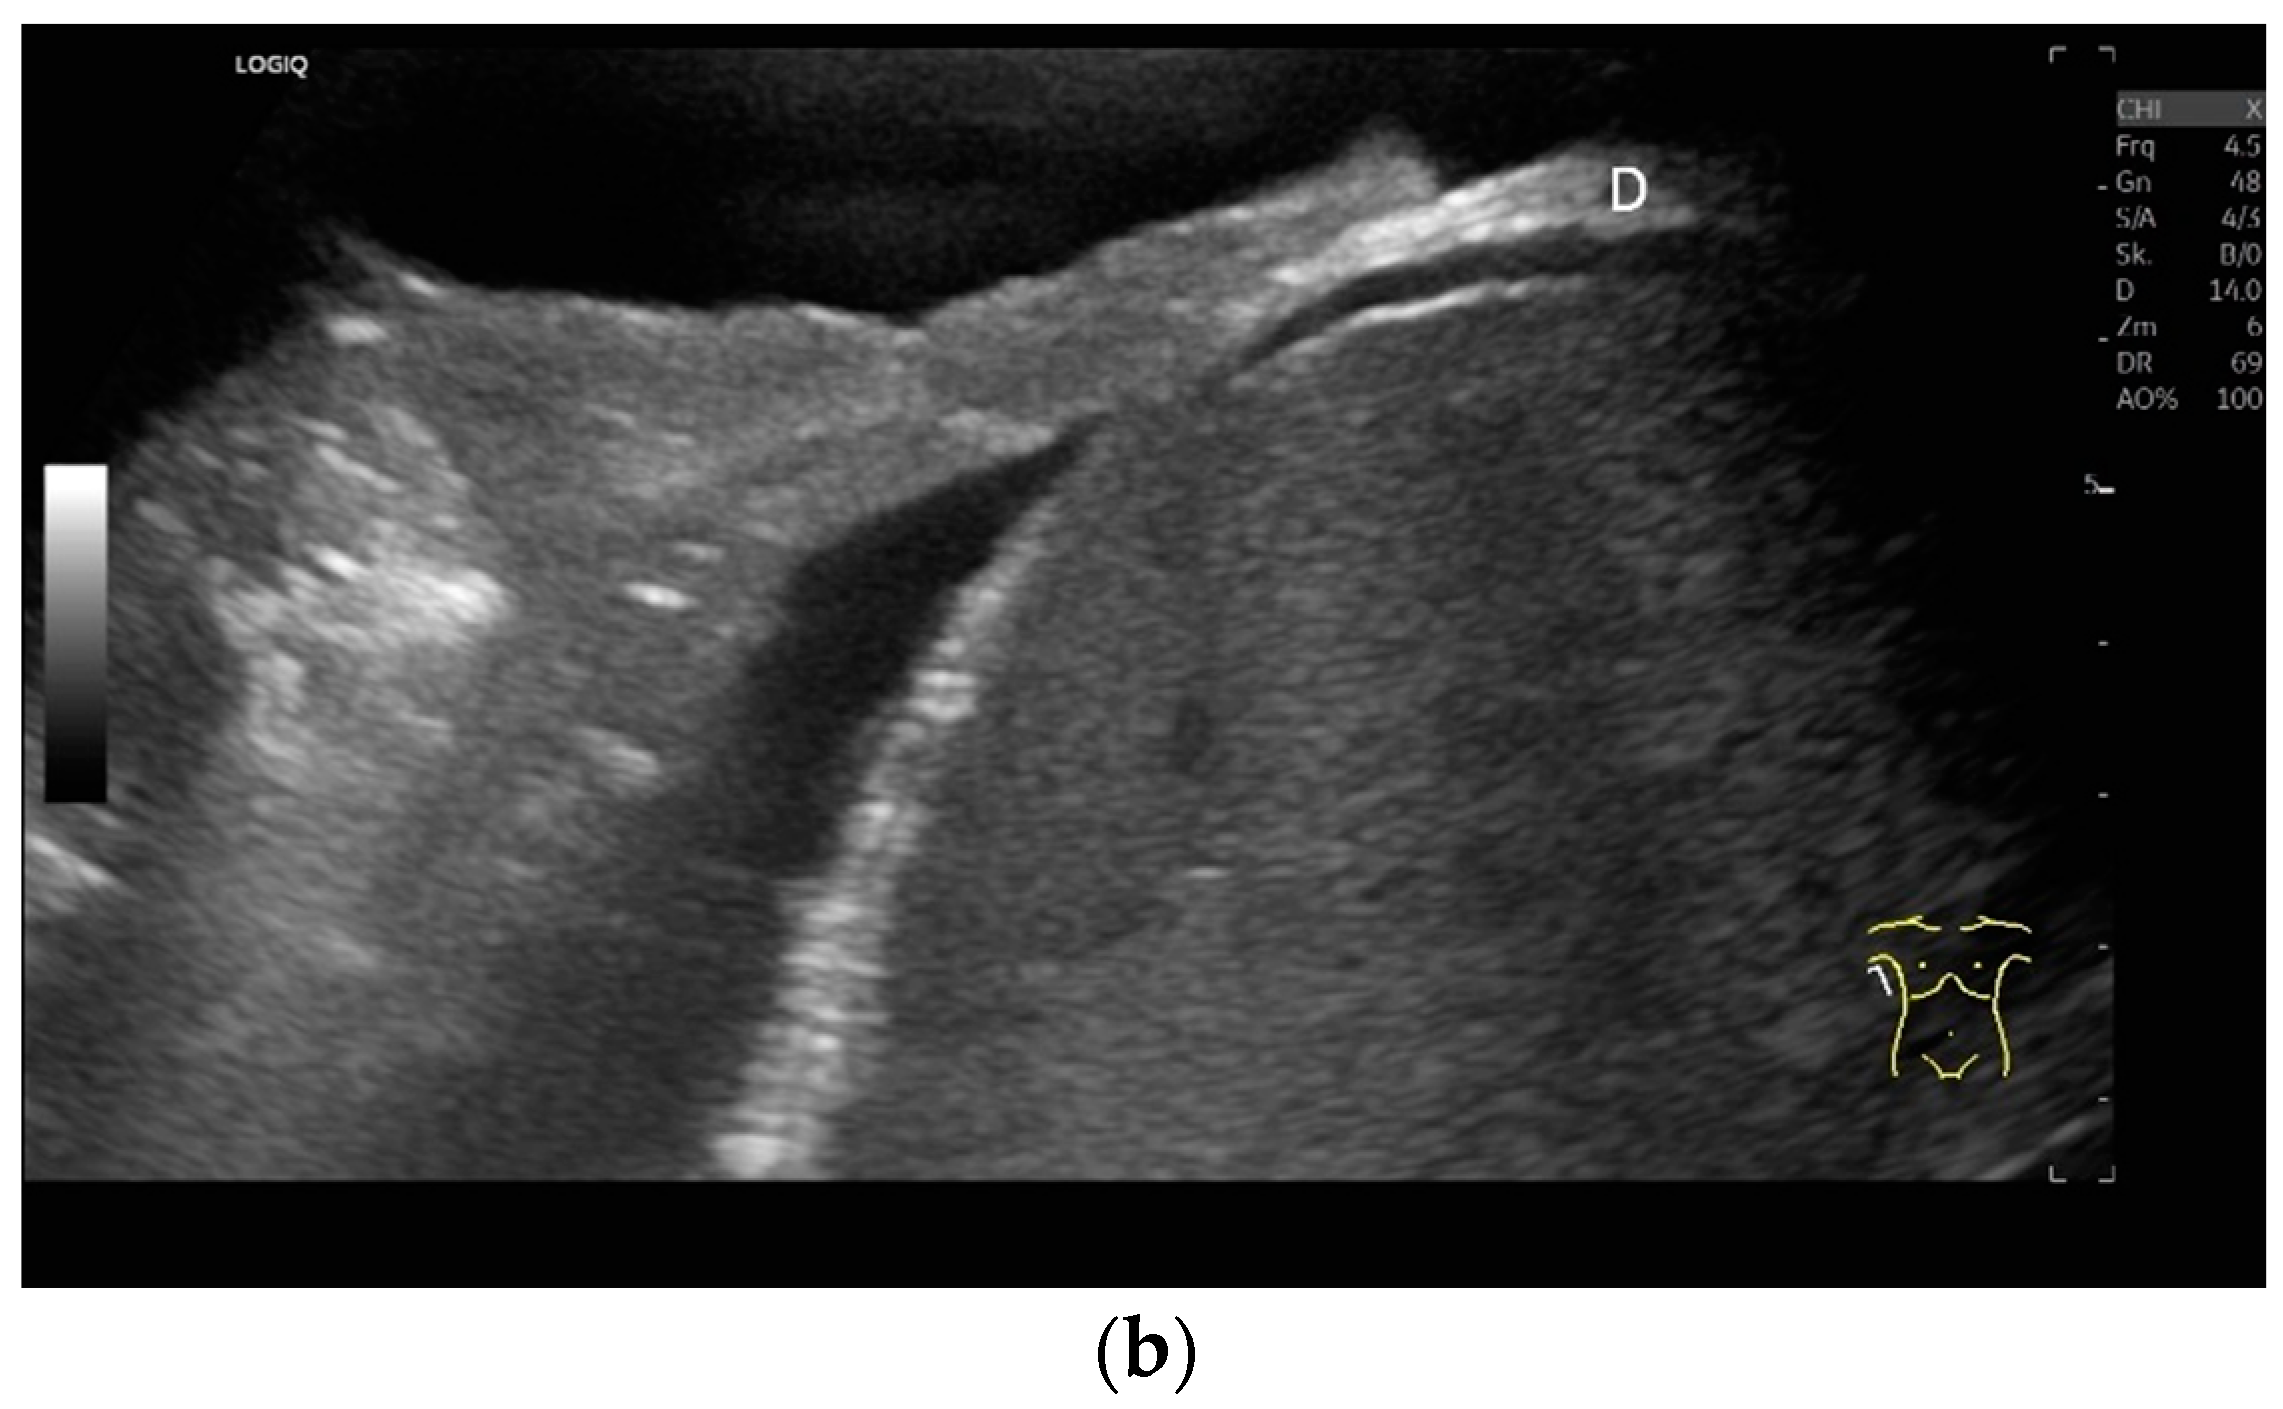

With high-resolution linear transducers, the diaphragm presents itself as a hypoechoic band. It is covered on both sides by a very thin hyperechoic layer. This corresponds to the peritoneum and the parietal pleura, respectively. Depending on the resolution, a further delicate hyperechoic layer is usually visible centrally in the muscle, which is most often considered to be a fibrous layer in the center of the diaphragm (Figure 1).

Lateral transducer position in the zone of apposition: The transducer is positioned longitudinally and laterally in the area of the mid-axillary line or slightly ventral to it between the anterior and mid-axillary lines, approximately in the 8th or 10th intercostal space. The diaphragmatic reflex is located on the inner side of the ribs below the pulmonary glide with pulmonary reverberations. This localization of origin of the diaphragm from the inner side of the rib cartilage is referred to as the zone of apposition (Figure 3). As this localization is only a few centimeters below the skin surface, high-resolution linear transducer use is highly recommended. In this position, the diameter of the diaphragm is measured during inspiration and expiration [2,3,4,5] (Figure 4). The thickness of the diaphragm varies, with caudal parts being thicker than cranial parts. The measurement of diaphragm thickness is highly variable depending on the intercostal space chosen, with thickness varying by up to 6 mm between the intercostal spaces [6]. It is therefore important to select the same position for comparable measurements and, if necessary, to mark the location for the transducer position [7]. Obesity limits assessment of the diaphragm [2].

Subcostal transducer position: An abdominal sector or cardiac transducer (2–5 MHz) is used in the subcostal window. This position is used to assess diaphragmatic excursion. The transducer is placed between the linea medioclavicularis and linea axillaris anterior. The diaphragmatic excursion can then be visualized and measured in M-mode (Figure 5). The gallbladder and inferior vena cava are important landmarks. It is important to guide the ultrasound probe as perpendicularly as possible. The M-mode axis should meet the diaphragm at an angle of 90%. In this position, diaphragm thickness in inspiration and expiration can also be measured using M-mode, and diaphragm shortening can be calculated. However, in normal adults, the diaphragm can usually only be visualized in this position using abdominal sector transducers and is less accurately delineated than with a linear transducer from the lateral side in the anterior axillary line.